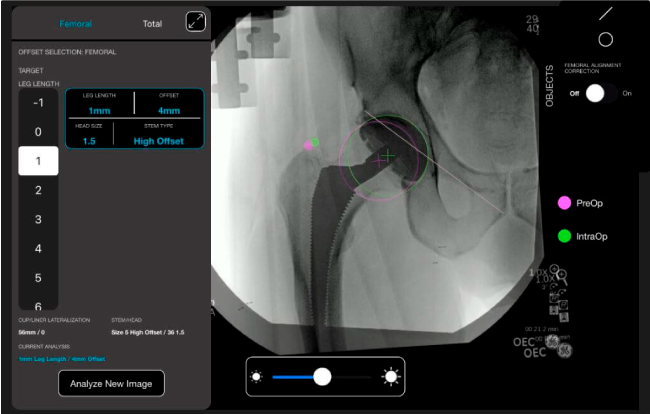

Desplazamiento y offset para posicionamiento óptimo del componente (vástago) femoral.

Verificación de la posición deseada del implante que potencialmente puede ayudar a reducir la probabilidad de dislocación protésica y aumentar la estabilidad de la articulación.

Anotaciones digitales y herramientas de análisis de longitud de pierna.

Con tecnología ONETRIAL® que calcula automáticamente el cambio en la longitud de la pierna y el desplazamiento para todas las combinaciones de implantes en una tabla fácil de leer.